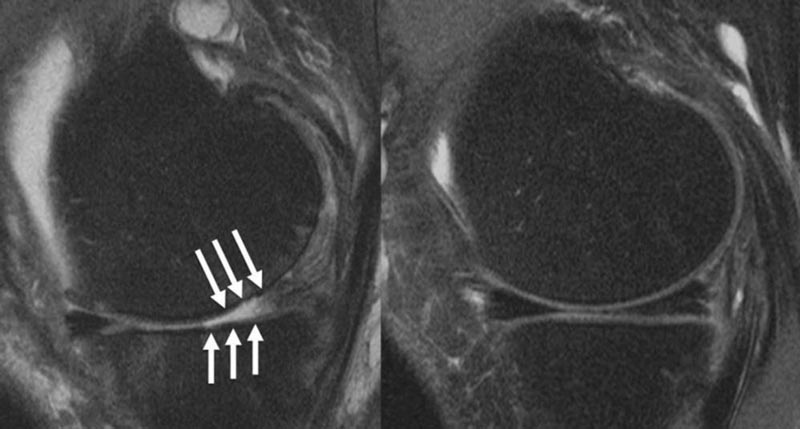

Articulation du genou d’un patient présentant (A) de graves défauts cartilagineux et (B) une articulation du genou intacte.

Une IRM a été réalisée chez tous les patients au moment de l’injection et deux ans avant et après. Les IRM ont été évaluées à l’aide du Whole Organ MRI Score (WORMS), un système de classification de l’arthrose du genou qui se concentre sur le ménisque, les lésions de la moelle osseuse, le cartilage, les épanchements articulaires et les ligaments. . Les chercheurs ont identifié la progression de l’arthrose en comparant les scores d’imagerie des examens de base et des examens de suivi de deux ans.

L’analyse statistique a montré que les injections de corticostéroïdes dans le genou étaient associées de manière significative à la progression globale de l’arthrose du genou, en particulier au niveau du ménisque latéral, du cartilage latéral et du cartilage médial.